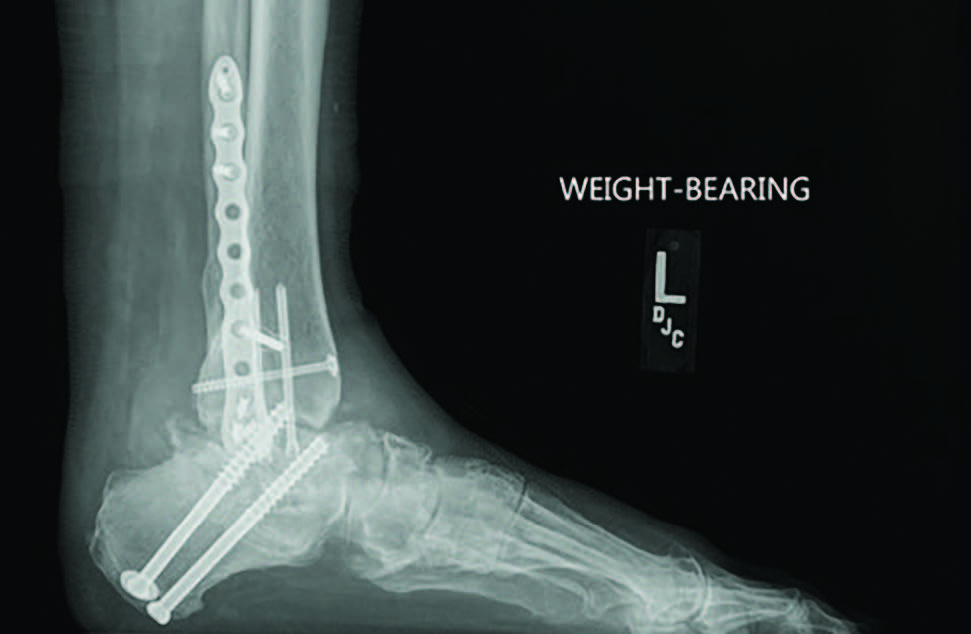

Radiographs demonstrated a subtalar joint dislocation with advanced degenerative changes (see first two images above). As we prepared for a subtalar joint fusion, we emphasized medical optimization of her vitamin D levels and made sure to rule out any metabolic weaknesses that would alter our techniques in the operating room. In my experience, it is best to perform these complex cases at facilities that can provide comprehensive patient care and possible admission if necessary.

For this patient, I ultimately performed a subtalar joint fusion with distal tibial autograft. She subsequently went on to develop a symptomatic non-union at six months postoperatively and collapse of her talus (see third image above). She again had medical optimization and we planned for a femoral head allograft reconstruction with Augment bone graft and intramedullary nail fixation. The patient went on to clinical success and there was demonstrated healing on a CT scan at four months post-op. She is now weightbearing in a shoe at two years post-op (see fourth and fifth images above).